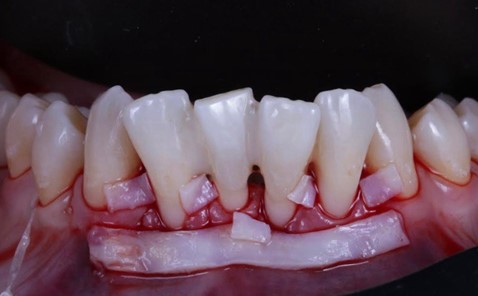

Вверху фото десны с рецессией до операции, а внизу — после операции

На начальных этапах, пока рецессия не дошла до тканей пародонта, вернуть всё к норме можно достаточно быстро, качественно и относительно дёшево. Если же десневые сосочки между зубами атрофировались, пересаживать лоскуты слизистой с нёба, чтобы нарастить десну, придётся гораздо дольше и дороже.

Можно сравнить эстетику до и после